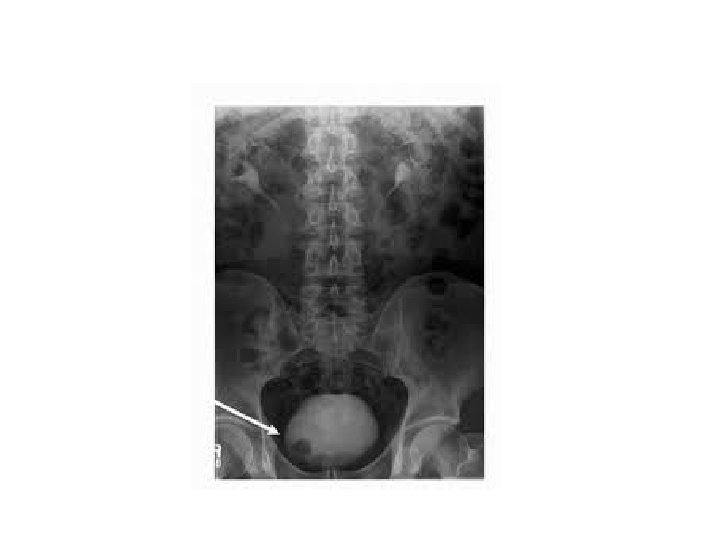

ultrasound